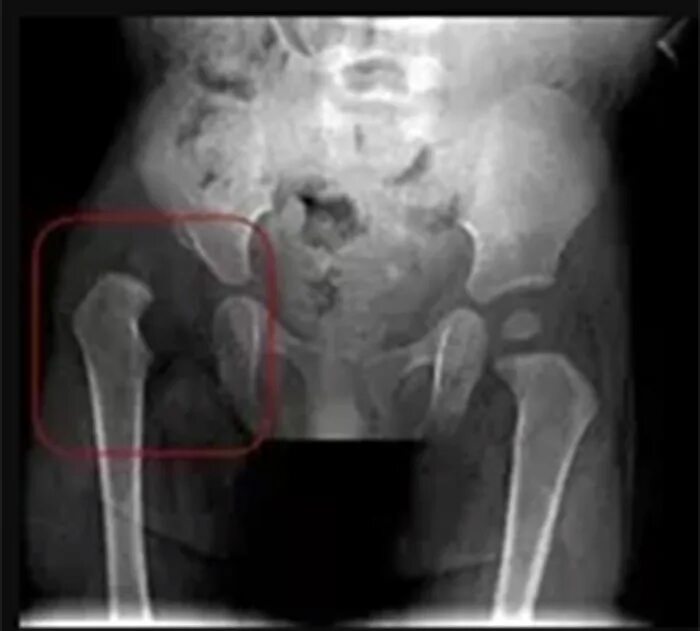

Подвывих тазобедренного сустава у взрослых